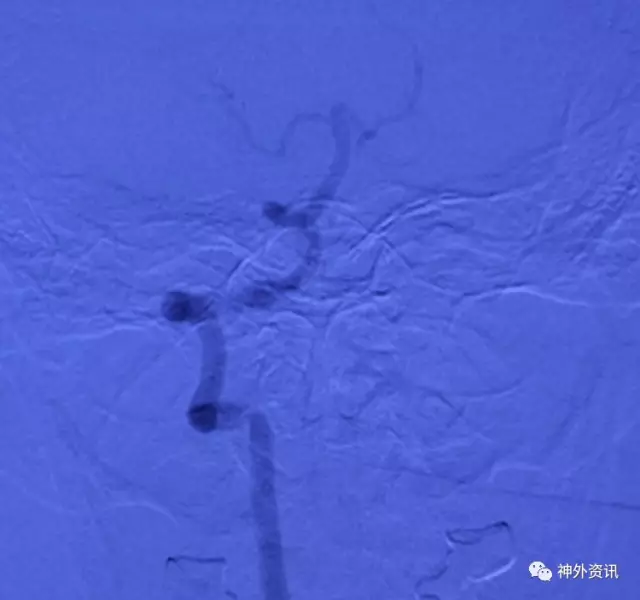

复合手术室一期造影,VA开口通畅,远端血管呈低灌性狭窄

L-VA颅内正侧位造影示pⅠCA显影好,正位示供血双侧,看来病人头晕的缺血症状该结束了

一月后CTA复查,左椎A开口无狭窄,远端管腔变粗,低灌注造成的狭窄明显改善,病人症状完全缓解